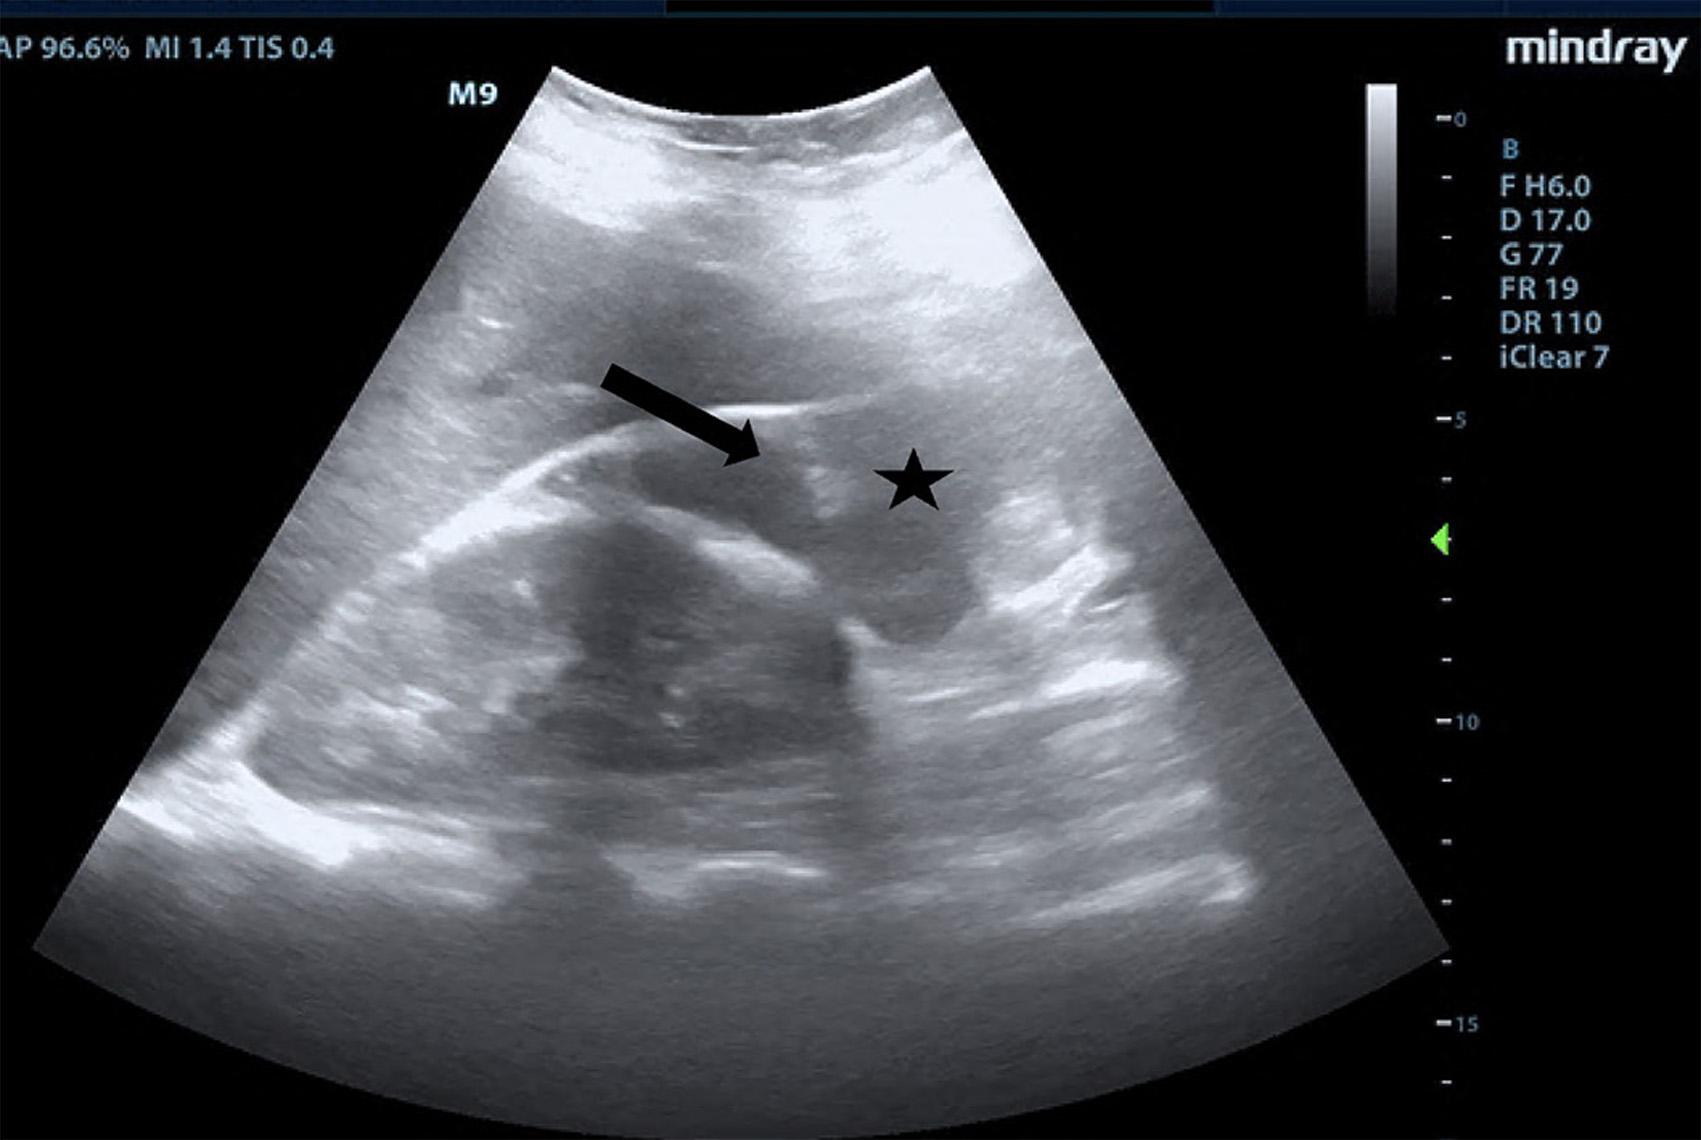

Onphysicalexamination,thepatienthadanoral temperatureof99° Fahrenheit(37.2° Celsius),tachycardiaof 108beatsperminute,bloodpressureof106/71millimetersof mercury,97%oxygensaturationonroomair,andadiffusely tenderabdomenwithvoluntaryguardingandrebound tendernesssuggestiveofperitonitis.APOCUSwas performedtoassessforintraperitonealfree fluid.Itrevealeda complexcollectionof fluidwithinternalechoesinthe hepatorenalspaceraisingconcernforaloculatedinfection (See Image and Video).

Abdomino-pelvicPOCUSmayguidetriage,diagnosis, andmanagement,assistingtheclinicianininvestigatinga rangeofdiseaseentitiesincludingbiliarypathology, abdominalaorticaneurysm,orTOA.3–5 Bedsideultrasound isgenerallyreadilyavailableintheEDsettingandmayserve asanadditionalmodalitytoidentifyunusual findingsearlyin thepatient’sclinicalcourse.Itdoesnotrequireionizing radiationandisnottimeintensivetoperform.Cliniciansmay considerearlyuseofPOCUSforperitoneal findings,as evidencedinthiscasepresentation.Inconjunctionwith informationobtainedonhistoryandphysicalexamination, theunusual,rightupperquadrantPOCUS findingsof intraperitoneal fluidwithloculationscausedconcernfora disseminatedpelvicinfection.Thiswasconfirmedasa rupturedTOAwithamoderateamountofpurulent, intraperitonealfree fluidontheoperativereport.Fitz-HughCurtissyndromewasaconcerngiventhecomplicated fluidvisualizedwithPOCUS,buttherewasnocommentof violin-stringadhesions,adhesions,or fibrousadhesions betweentheanteriorhepaticcapsuleandparietal peritoneumnotedonthelaparoscopicoperativereport, althoughitisunknownwhetherthisanatomicarea wasevaluated.

Intraperitoneal fluidiseasilyvisualizedonultrasound, andwhencomplex fluidwithloculationsisencountered,the differentialdiagnosisincludesmalignancy,inflammation, andinfectiousprocesses.6 Similar findingsofseptated intraperitoneal fluidhavebeendocumentedincases of Ctrachomatis inPID,7 cholecystitis,8 and tubercularperitonitis.9

GroupAstreptococcusisararecauseofpelvic in fl ammatorydisease,usuallyseenintheperipartum period,inpatientswithanIUDorwhohavehadother recent,invasivegynecologicprocedures.Inapatientnot respondingtoantibioticsadministeredfortypicalPID coverage,GASshouldbeconsideredasapossibleetiology andapenicillin-basedantibioticadministeredtoprevent progressiontotubo-ovarianabscessformation,peritonitis, andsepsis,particularlyincasesofreturningpatients previouslytreatedwithantibiotics.Bedsideultrasound shouldbeperformedinpatientspresentingwithabdominal pain,anduncommon fi ndingsshouldtriggerfurther investigation.Toourknowledge,noothercasesofloculated fl uidinthehepatorenalspaceassociatedwithPIDhave beenreported.

Video. Rightupperquadrantultrasonographyusingcurvilinear probefanningthroughthecoronalplanedemonstratingascitesand septationsinapatientultimatelydiagnosedwithpelvic inflammatorydisease.